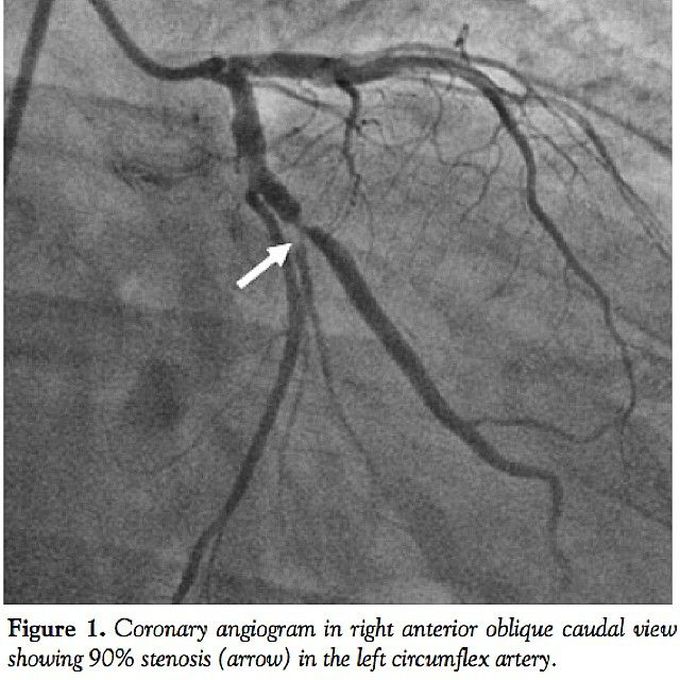

A coronary angiogram showing stenosis of the left circumflex artery